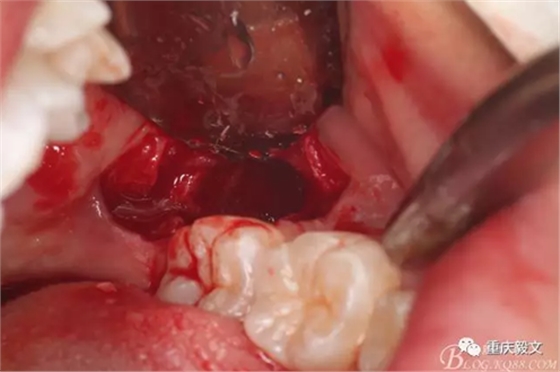

圖8.挺出牙冠的遠(yuǎn)中部分。然后取出近中部分。拔牙要點(diǎn):注意保護(hù)鄰牙,以挺力為主。